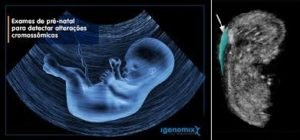

O diagnóstico dessa alteração genética é feito ainda na gravidez, através de alguns exames como: ultrassonografia (morfológica), translucência nucal (medida tirada na região da nuca do feto, no ultrassom morfológico), cordocentese (amostra de sangue fetal) e amniocentese (amostra de líquido amniótico).

Cordocentese (à esquerda, exame feito através da coleta do sangue do feto) e Amniocentese (à direita, exame feito através da coleta do líquido amniótico materno).